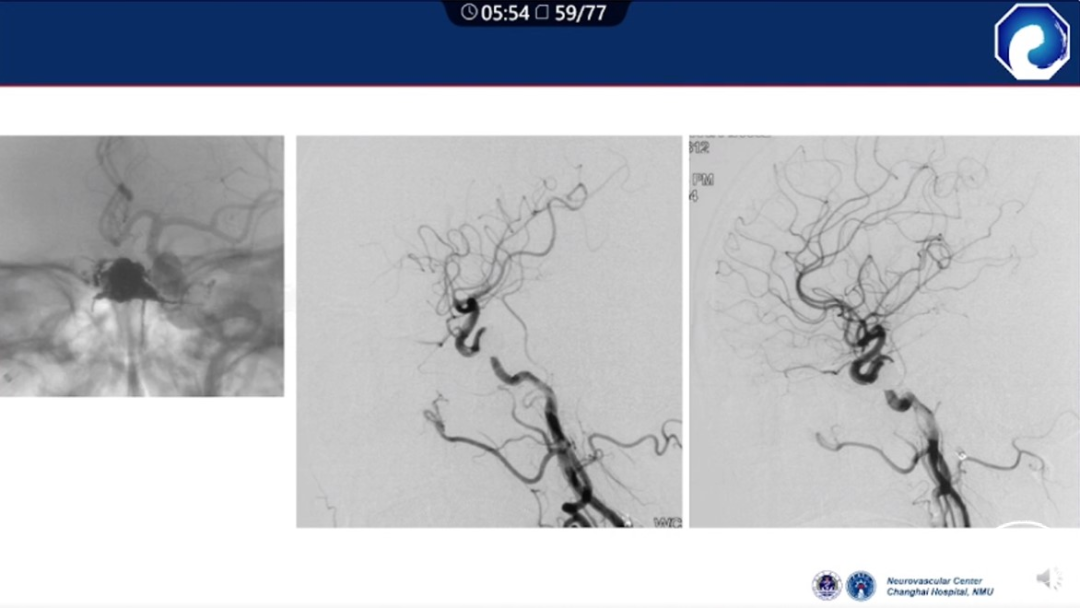

减少栓塞材料应用。

减少与颈内动脉重叠,避免栓塞材料意外栓塞。